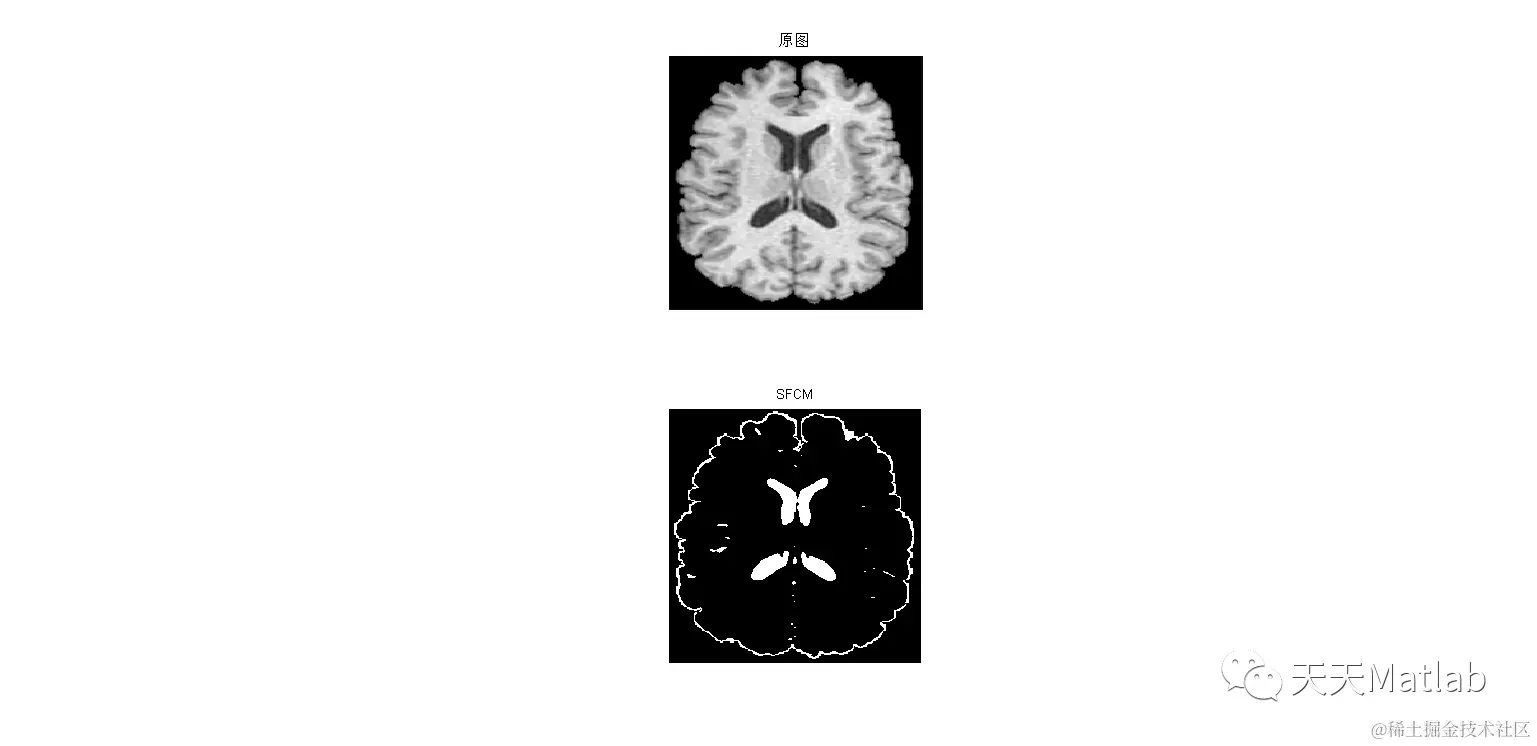

【图像分割】基于空间信息的模糊均值聚类算法实现图像分割matlab代码

针对传统的模糊C-均值(FCM)算法没有考虑图像像素的空间邻域信息,对噪声敏感,算法收敛较慢等问题,该文提出一种抑制式非局部空间直觉模糊C-均值图像分割算法。首先,通过计算像素的非局部空间信息提高抗噪能力,克服传统的FCM算法只考虑图像单个像素的灰度特征信息的缺陷,提高分割精度。其次,根据直觉模糊集理论,通过“投票模型”自适应生成犹豫度作为抑制因子修正隶属度,提高算法的运行效率。实验结果表明,该算法对噪声鲁棒性较强并且有较好的分割性能。

3 仿真结果